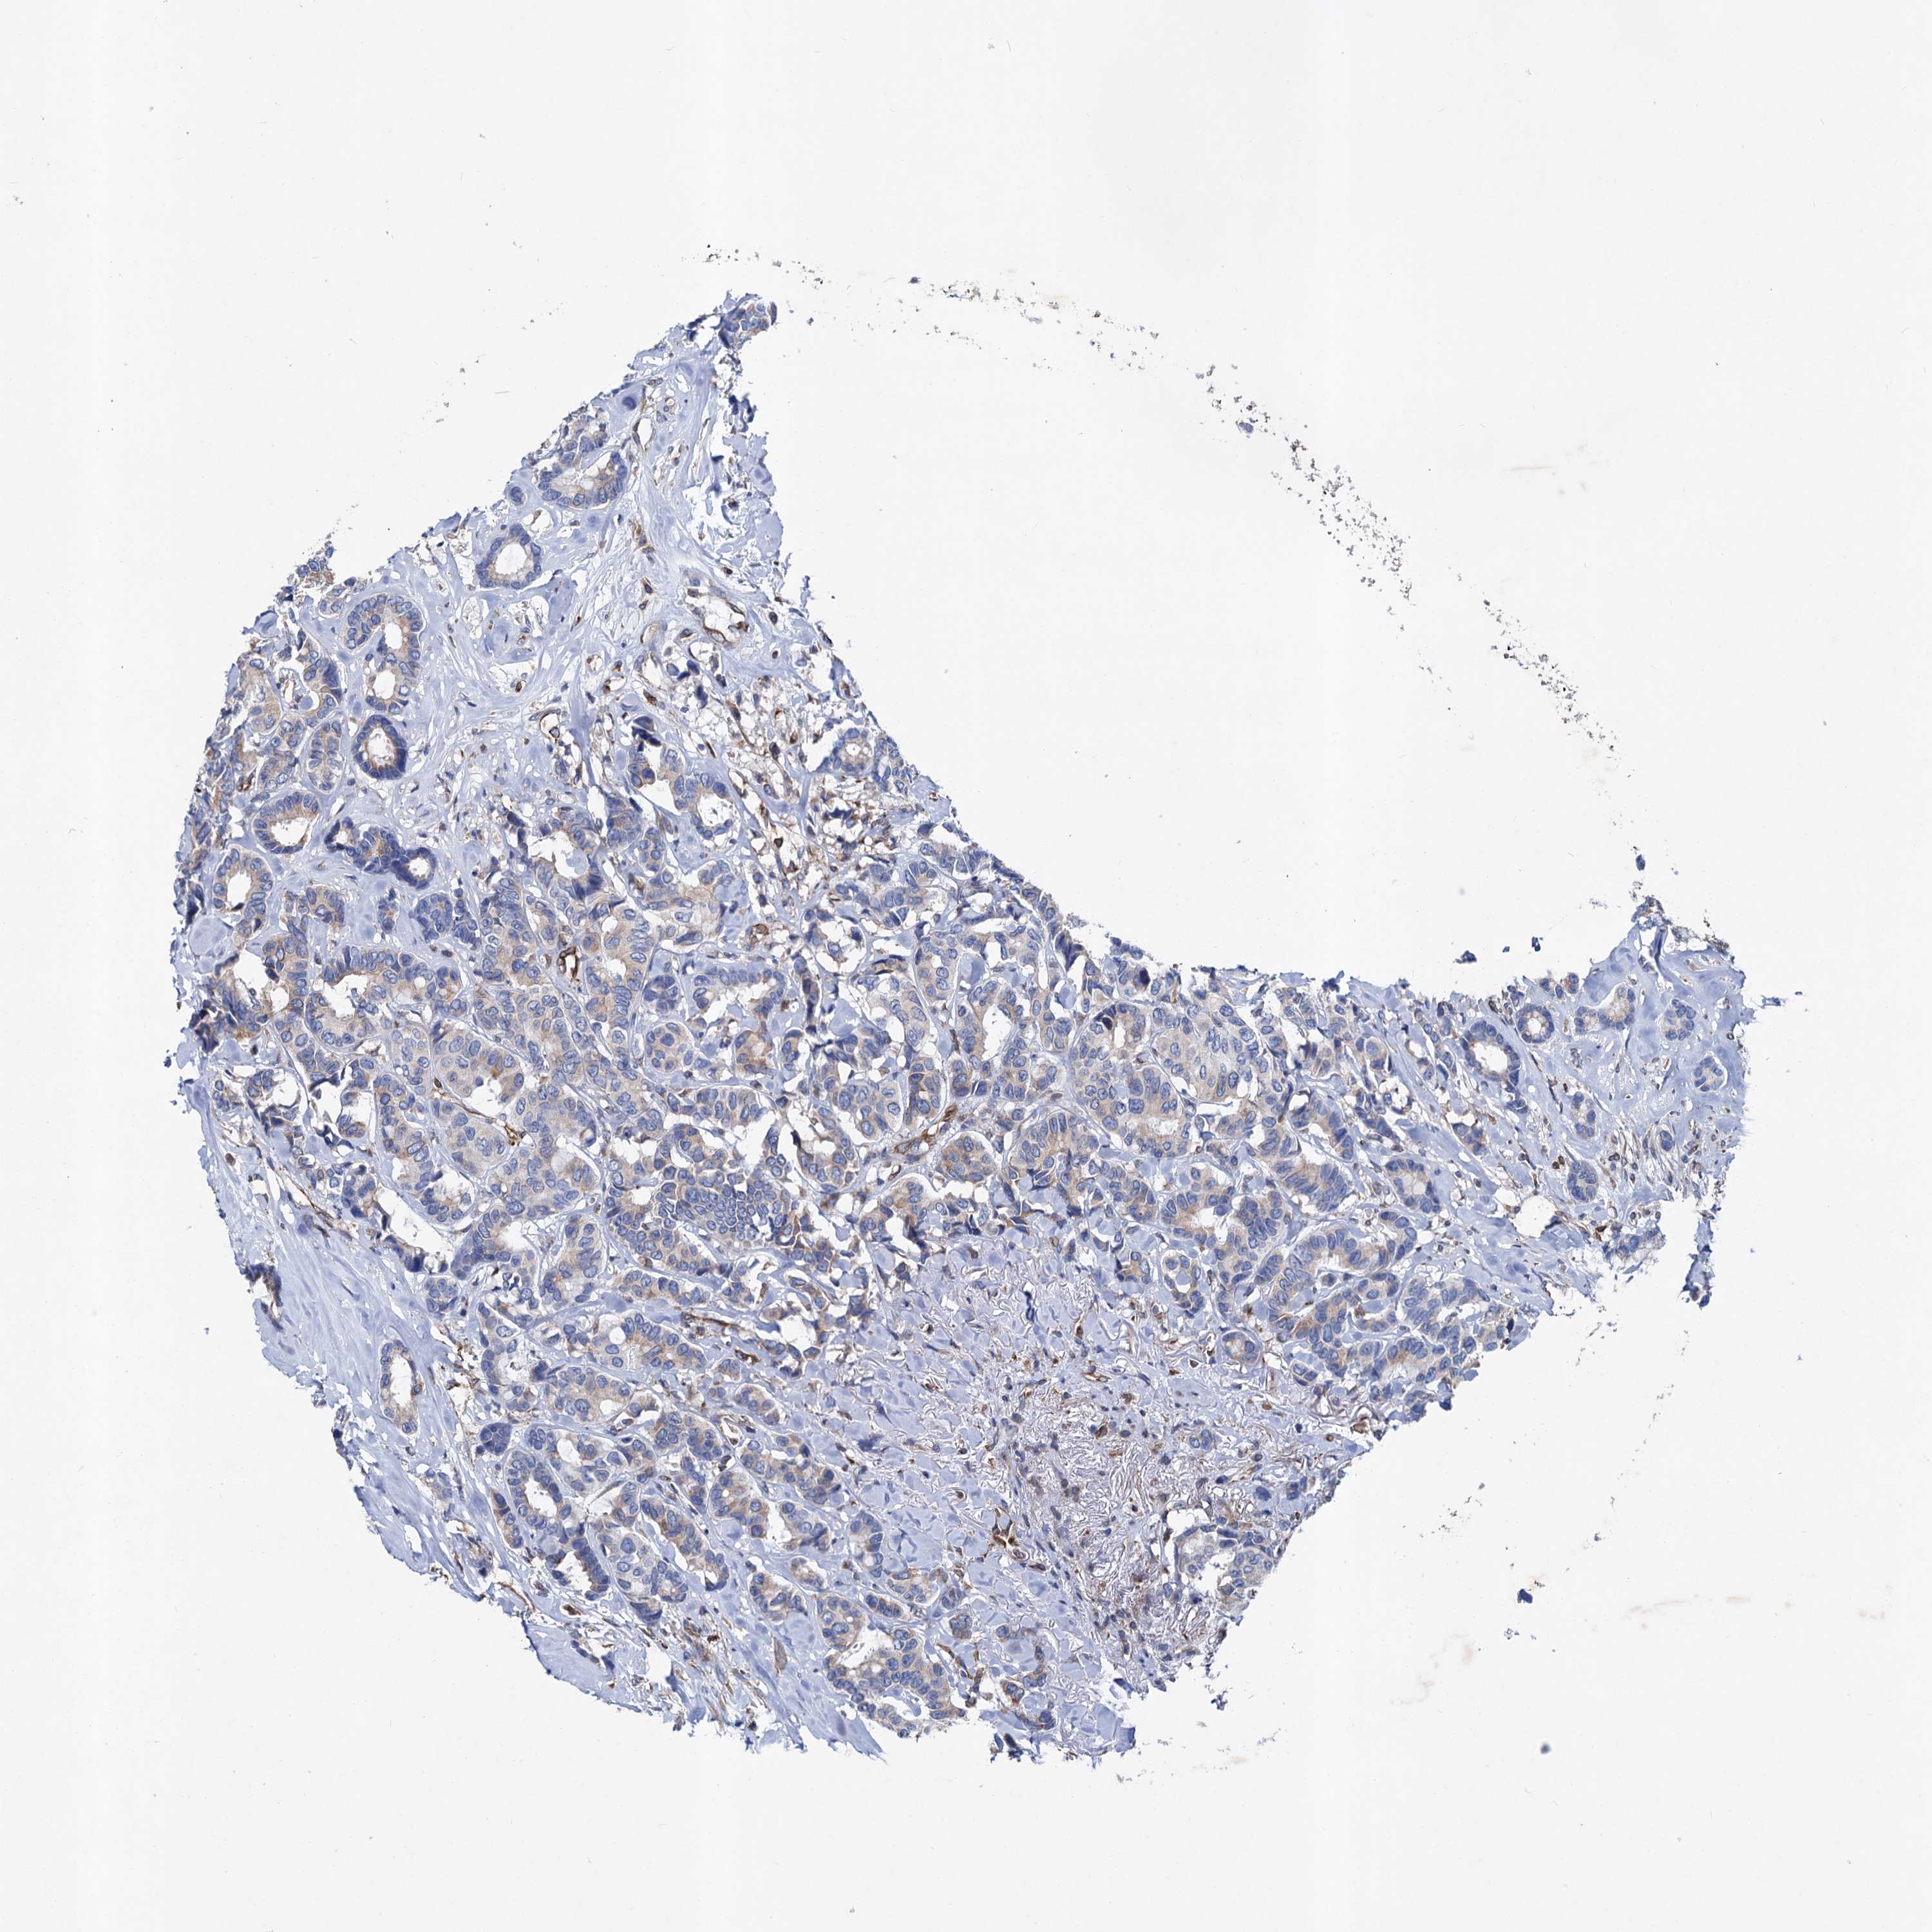

CANCER BREAST CANCER Show tissue menu

BRCA TCGA BRCA VALIDATION PROTEIN EXPRESSION